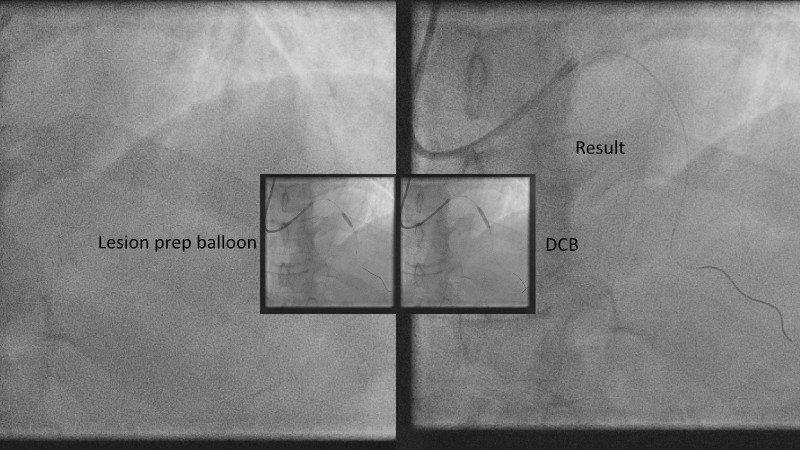

Explore cutting-edge strategies for optimizing drug-coated balloon (DCB) procedures in this session. Uncover practical tips to improve outcomes, review key indications, and examine international consensus on DCB use. Case presentations and expert discussions offer insights to refine your approach.

- To learn the tips and tricks to improve the result with drug coated balloon strategy